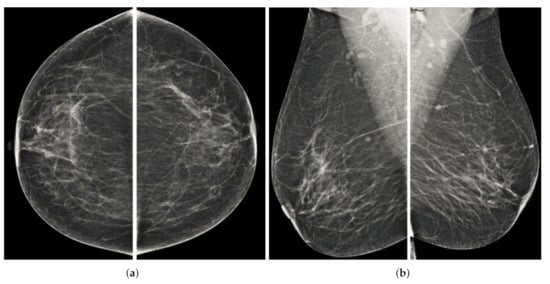

Computerized analysis of mammography is also challenging because one of the most important challenges is observing the pectoral muscles. The geometric shape of the pectoral muscles and their location depend on the mammographic images’ specific view [12,13]. There are two types of mammographic image views: the carnio-caudal (CC) view and the mediolateral oblique (MLO) view, and these views are shown in the Figure 1. The pectoral muscle on the CC view is semi-elliptical along the breast wall. In contrast, the MLO view covers most of the upper mammogram coverage and roughly corresponds to the overlapping right-angled triangle, as shown in Figure 1. Due to their appearance, both views suffered from low contrast, which made it difficult to see cancerous areas in some cases. Image enhancement requires correct observation and helps segment abnormal regions for disease classification. The quality of mammography images in terms of noise reduction and contrast enhancement is improved by using the image enhancement technique. The main purpose of implementing the image enhancement technique is to help the computerized breast cancer detection system to detect mammographic lesions with poor visibility and improve low contrast. Low contrast regions with small abnormalities are mostly hidden in the tissue of mammogram images, which makes it challenging to analyze the abnormal region, and also provides false detection.

Figure 1.

Representation of standard mammography views. The figure (a) represents the CC view of the right and left breast, and the figure (b) represents the MLO view of the right and left breast.